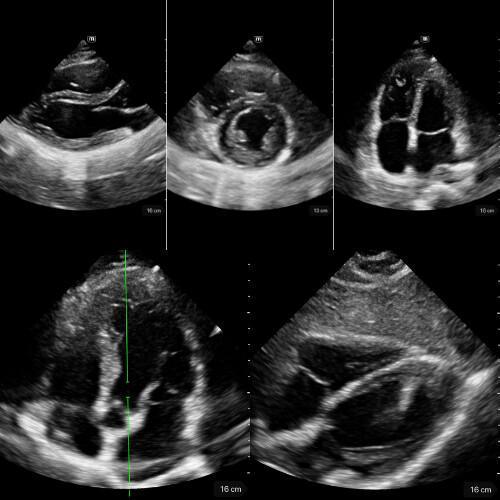

🔹 Vue Sous-costale (subxiphoïdienne)

→ Le cœur bouge-t-il ? y a-t-il du liquide ?

Placer la sonde sous l’appendice xiphoïde, dirigée vers l’épaule gauche, en s’aidant du foie comme amplificateur acoustique.

C’est la fenêtre universelle de la réanimation, utilisable pendant la RCP.

Elle permet de visualiser les quatre cavités, de détecter un épanchement péricardique même discret, et d’apprécier grossièrement la fonction myocardique.

Un simple regard suffit à trancher entre activité cardiaque présente ou asystolie réelle.